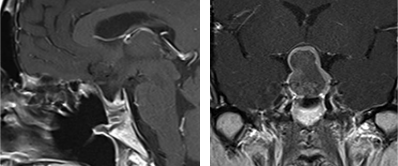

下垂体腺腫内視鏡単独経鼻的アプローチ

下垂体腺腫に対して内視鏡単独で経鼻的アプローチにより摘出術を施行。耳鼻科医と合同で行っている。(左)術中および術後MRIの所見。腫瘍被膜上に造影病変が認められているが、術後MRIでは消失している。術中MRI画像をナビゲーション用にアップデートし、残存腫瘍の摘出操作の際に役立てている。